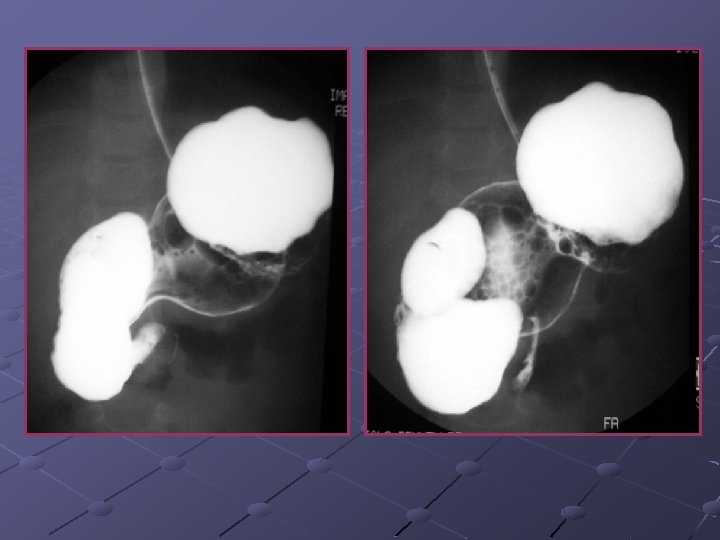

CAS N° 1 Nourrisson de 6 mois, sexe féminin Née à terme, T 21 Vomissements bilieux depuis 2 semaines Hypotonique, apyrétique Bilan biologique normal

Pneumatose gastrique (PG) révélatrice d’une sténose duodénale PG: entité rare mais connue depuis 1730 PG mécanique Traumatisme Endoscopie PG infectieuse Rupture intégrité gastrique Facteurs favorisants Sylverman Prise de caustique Ischémie gastro-int Strongyloïdose Obstruction E, D, G Air forcé à travers la paroi gastrique Mortalité = 30% Germes anaérobies envahissent la paroi gastrique Mortalité = 60%